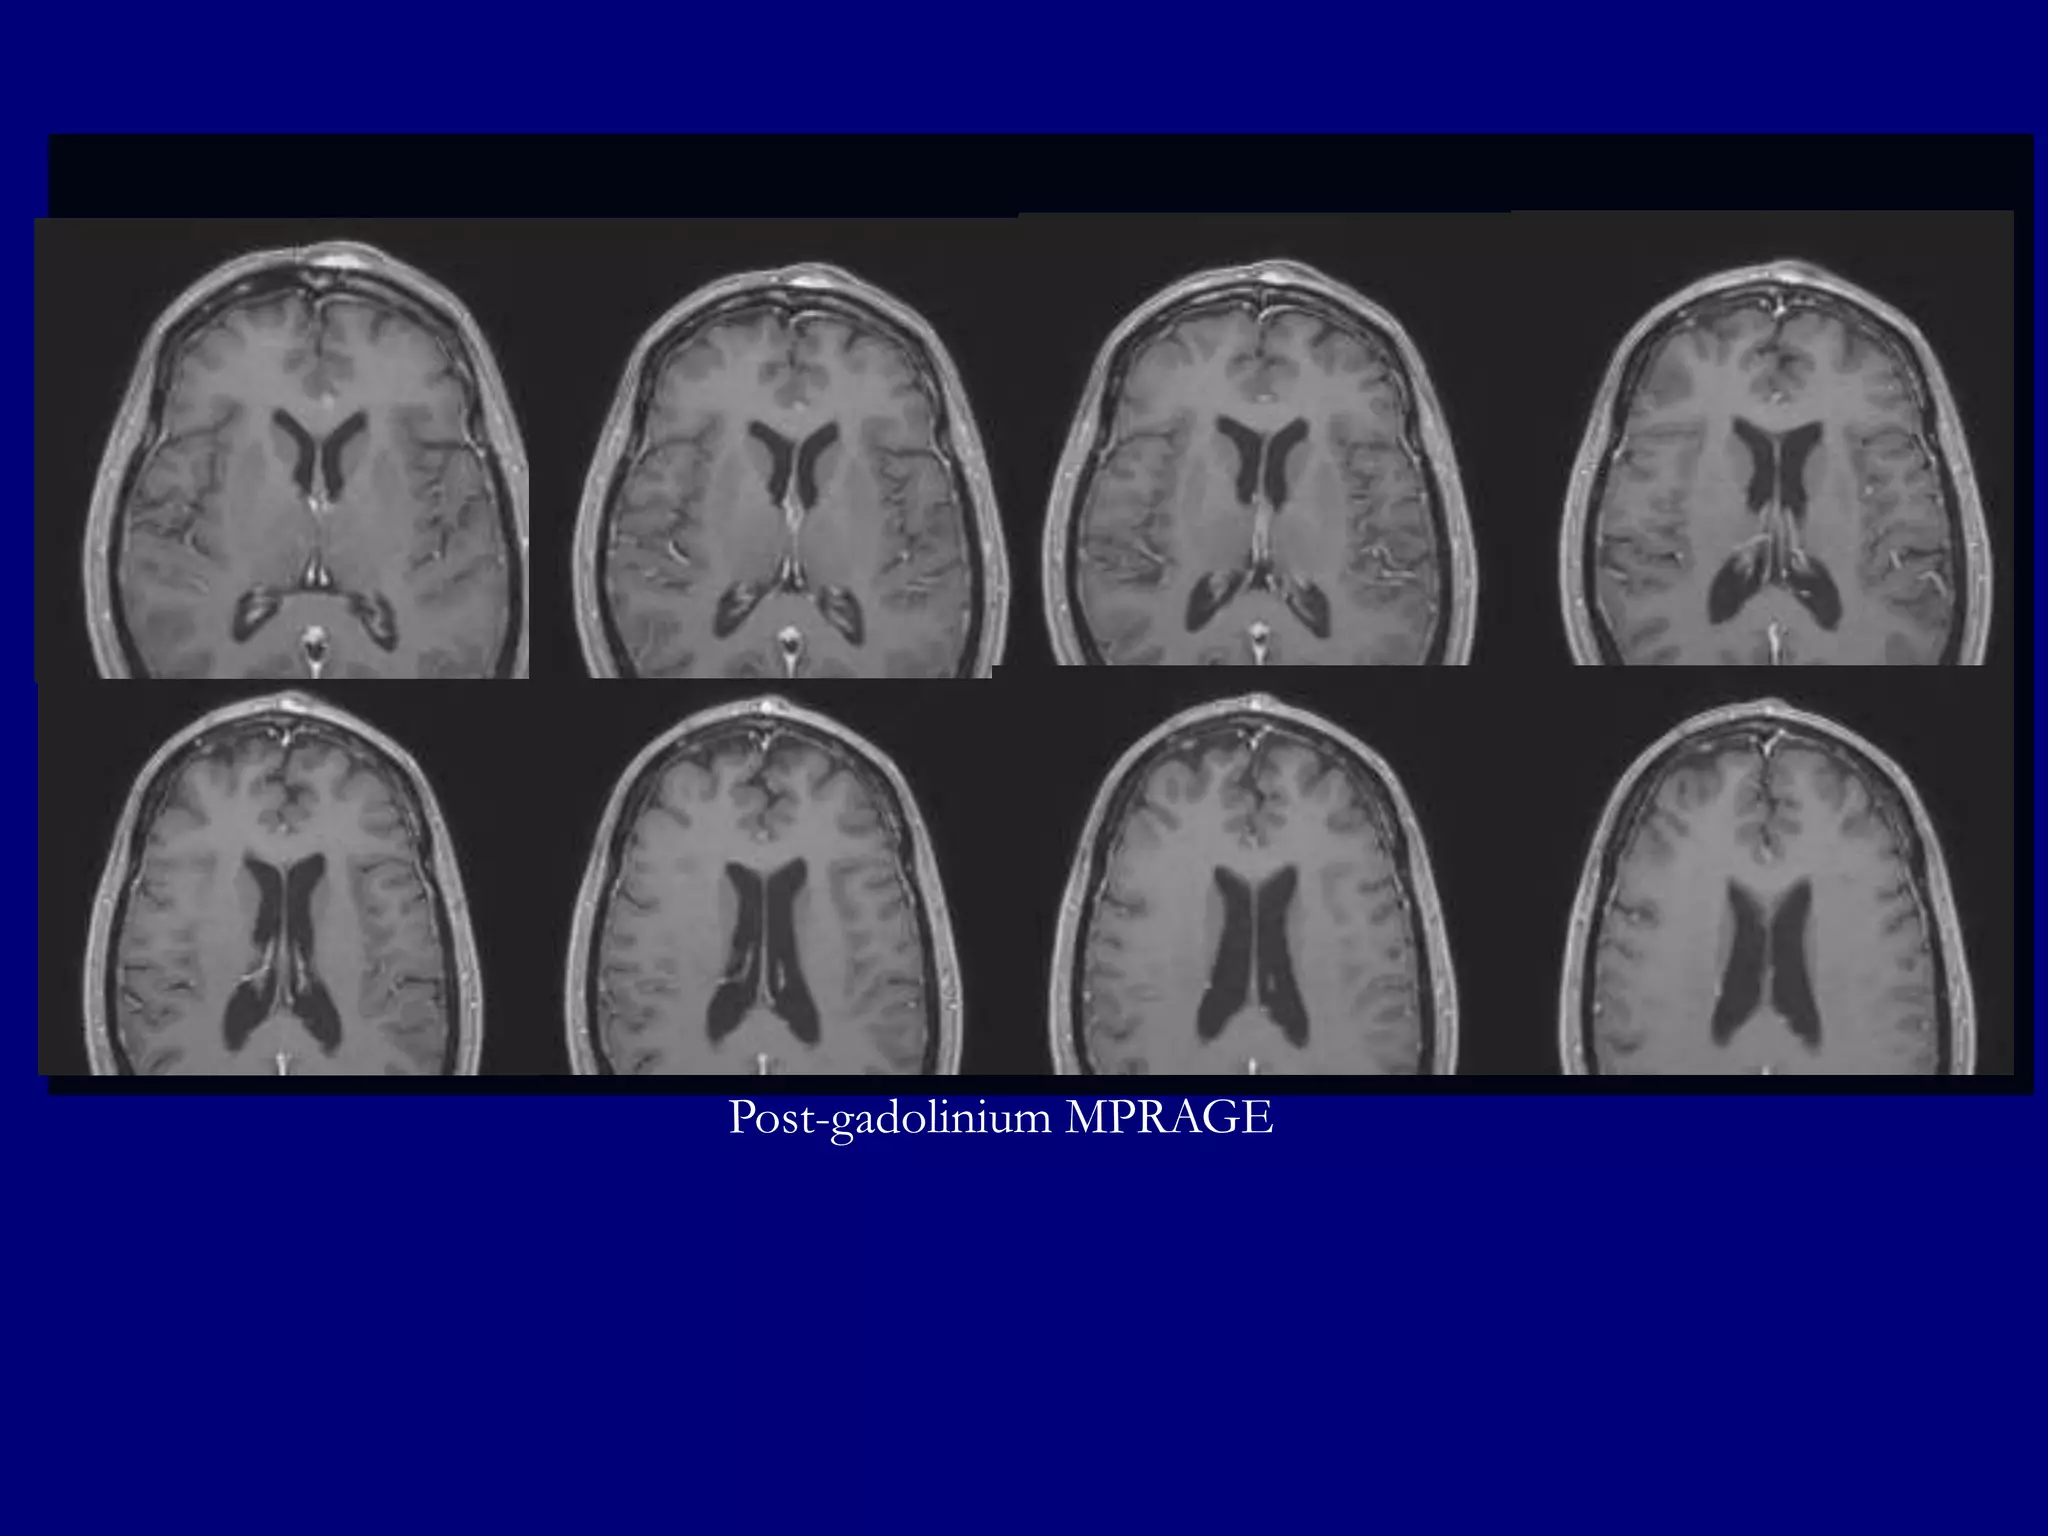

Post-gadolinium MPRAGE images for surgical planning

Post-gadolinium MPRAGE